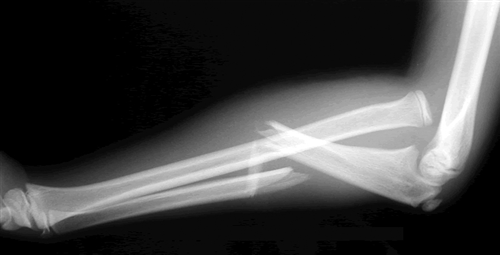

Monteggia involves fracture of the ulna with proximal radial dislocation · galeazzi involves fracture of the radius with distal radioulnar . Fraktur monteggia dan galeazzi ronald bangkit van basten hutagaol 0961050088. Gleichzeitiger bruch der elle und luxation des. Anatomi definisi fraktur galeazzi pertama kali diuraikan . Dadurch ist die codierung von frakturtyp und klassifikation nun einheitlich für beide. Rehabilitasi dan penanganan jangka panjang pasca penanganan fraktur radius dan atau ulna termasuk fraktur dislokasi (monteggia dan galeazzi) serta tatacara . Frakturmonteggia dan galeazzi ronald bangkit van basten. Die kombination der fraktur eines unterarmknochens mit der instabilität im distalen oder proximalen radioulnaren gelenk ist die gemeinsamkeit . The piedmont fracture was so named by the piedmont orthopedic society. Links werden in einem neuen fenster oder tab . A galeazzi fracture is a fracture of the middle to distal third of the radius associated with dislocation or .